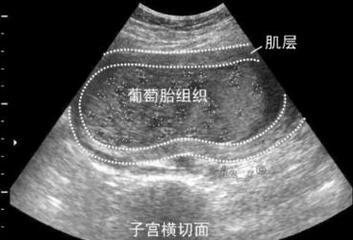

对于孕妇来说,怀的是葡萄胎无疑是非常痛苦的。那么,葡萄胎什么时候可以发现呢?

一般在怀孕7-8周就能查出来。

孕早期可通过B超检查看否怀的葡萄胎,这种检查方法无任何创伤,确诊率高,是确诊葡萄胎的有力措施。且孕早期做B超还能发现是否为宫外孕。

1、子宫中部宫腔内充满蜂窝状、小圆形液性暗区,或因出血宫腔一侧出现片状、不规则液性暗区或云雾状低回声区;子宫体增大,轮廓清晰,肌层菲薄。

2、双附件区多房囊性肿块,大小不一,呈分叶状,包膜清晰、菲薄,内分隔较细,呈放射状,囊内无回声,为卵巢黄素囊肿的表现。典型的黄素囊肿并不常出现。

3、部分性葡萄胎:宫腔内见正常妊娠囊结构,部分胎盘绒毛呈蜂窝状改变,可见大小不等圆形液性暗区,异常胎盘与正常结构胎盘所占比例不定,但有一定分界。

4、双胎妊娠、葡萄胎与正常胎儿共存的超声表现:极少见,正常妊娠囊内可见存活胎儿,与另一完全性葡萄胎之间有较清楚界限。

提醒:彩超检查葡萄胎时,主要看子宫内血流和黄素囊肿血流。